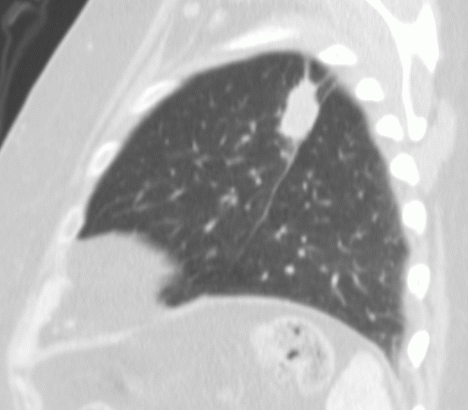

| Mittellappenatelektase rechts | 57-jähriger Mann mit einem Plattenepithelkarzinom

des re Oberlappens und Atelektase der Mittellappens. ![]() |